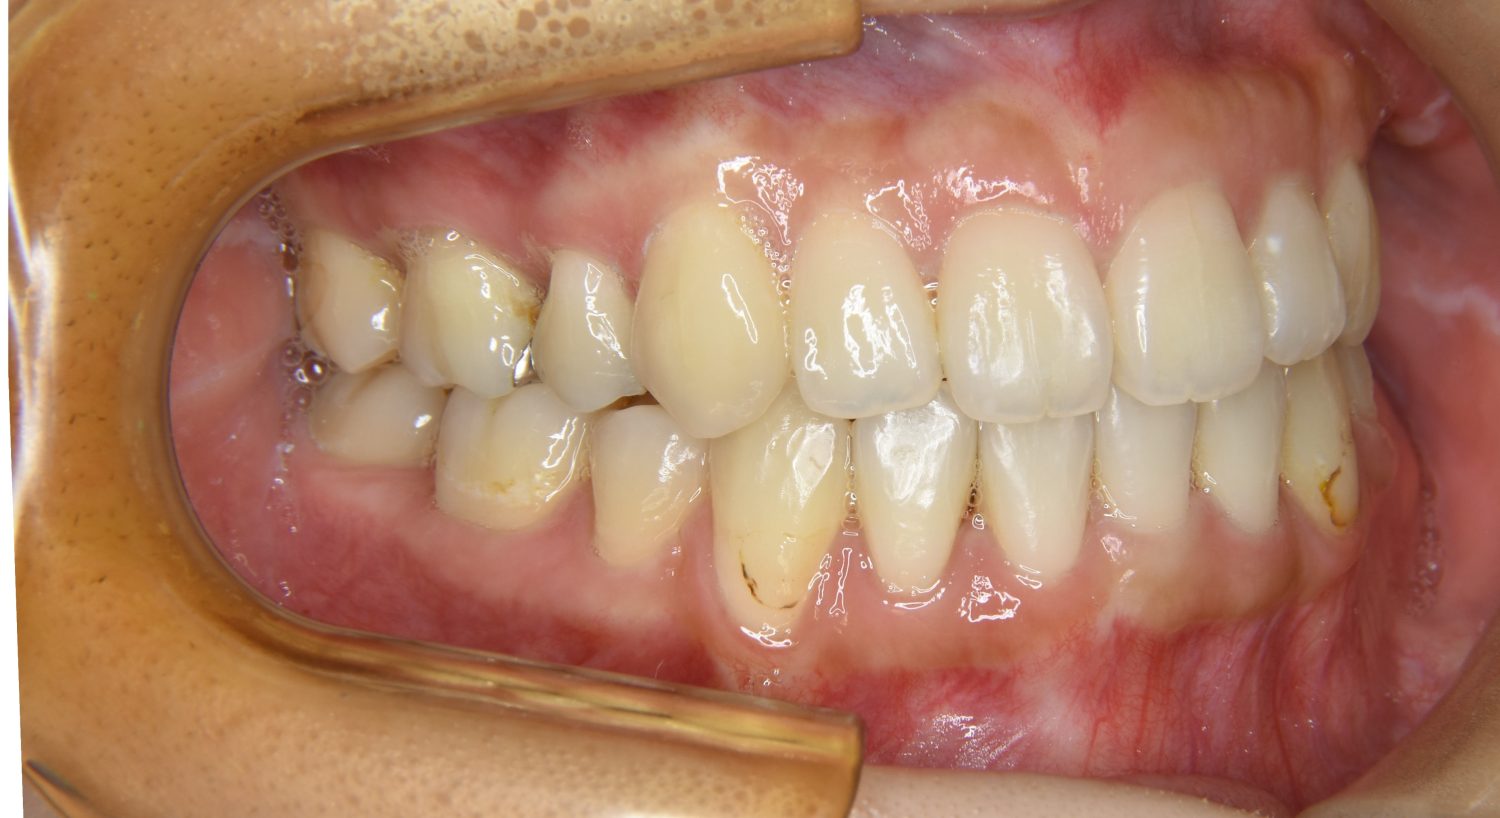

上顎前突の症例紹介①

Before

After

主訴

上の歯が出ている。歯並び全体が気になる。

治療内容

上顎両側第一小臼歯を抜歯し、上下ラビアルブラケット(唇側装置)に矯正用アンカースクリューを併用し治療を行いました。

治療費

1,000,000 円(税込)

治療期間

26ヶ月

通院回数

25回

想定されたリスク

※なし

丸山和宏先生

ピーススマイル矯正歯科

上顎前歯の前突により口元の突出が認められました。上の左右の第一小臼歯を抜歯し上顎前歯を後退させることで口元の突出感は改善し、咬合も良好な状態となりました。